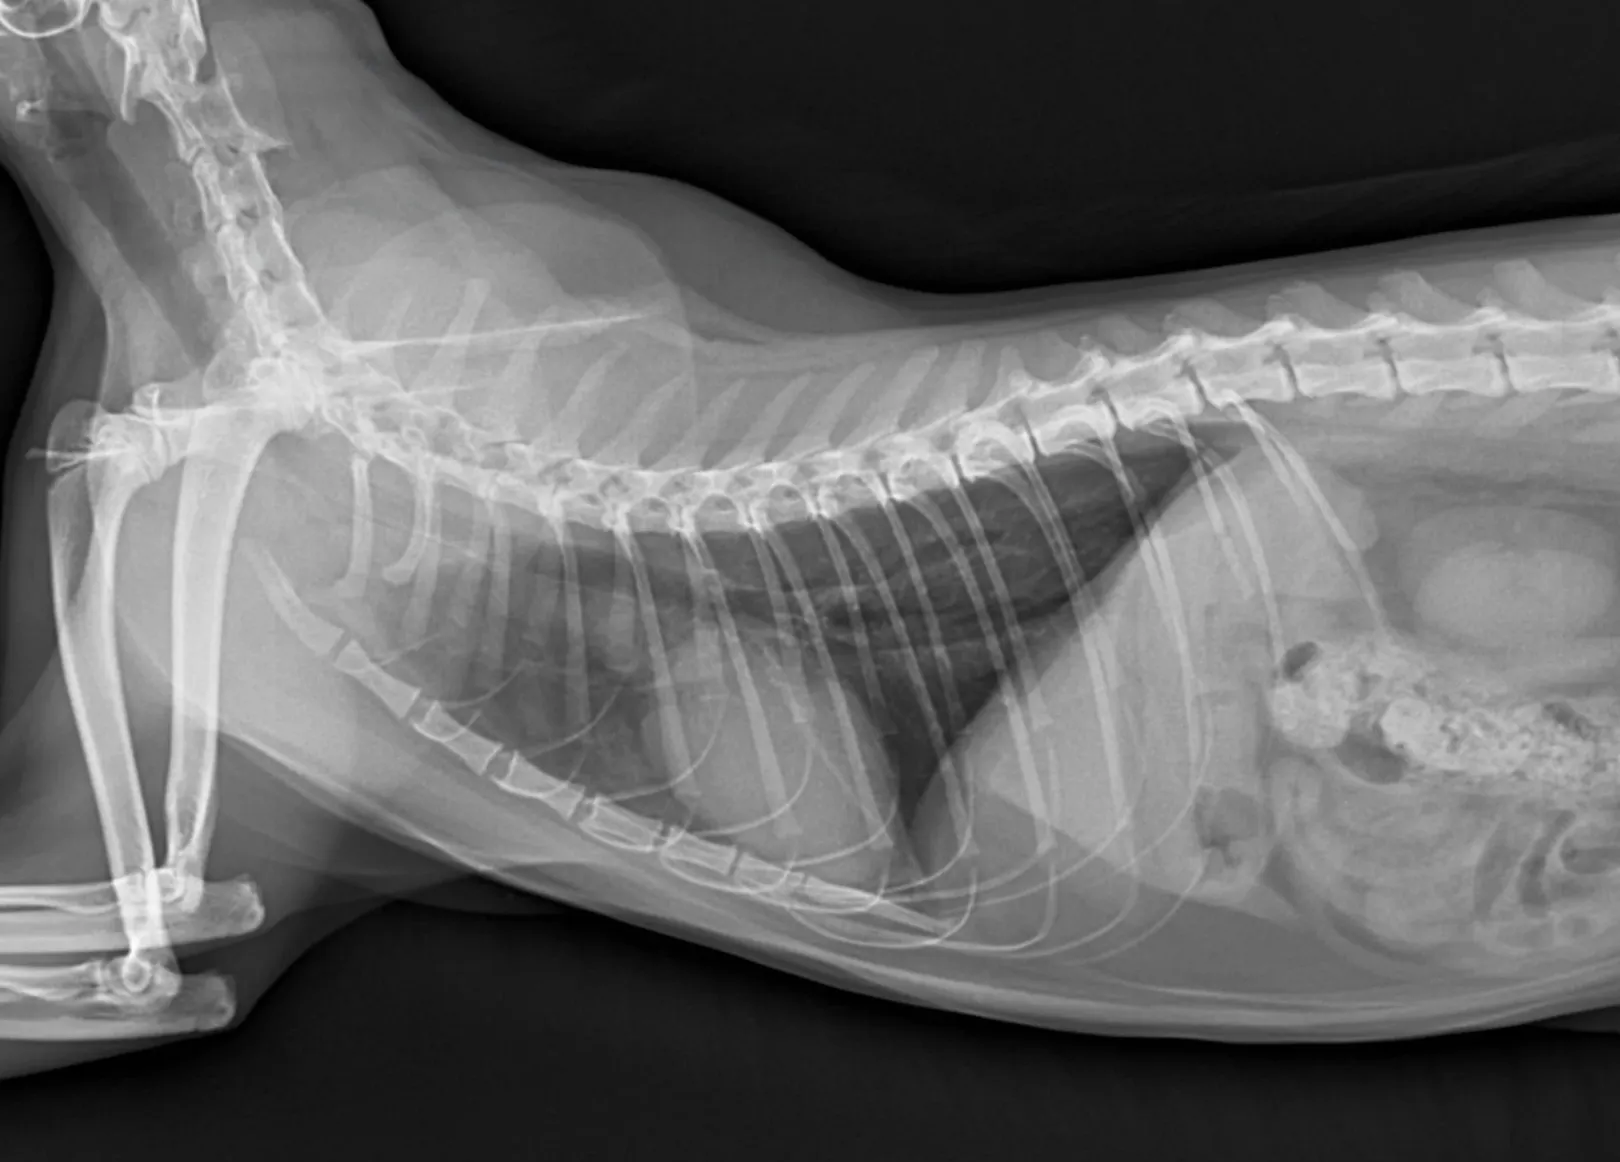

1. 엑스레이 검사 결과 (흉부, 복부)

1) 흉부 방사선

흉부 방사선의 영상 전공의 소견은 다음과 같습니다.

- VHS 7.3 (심장크기 정상)

폐실질, 폐혈관 특이 소견 없음

2) 복부 방사선

복부 방사선 상 특이사항 없었습니다.